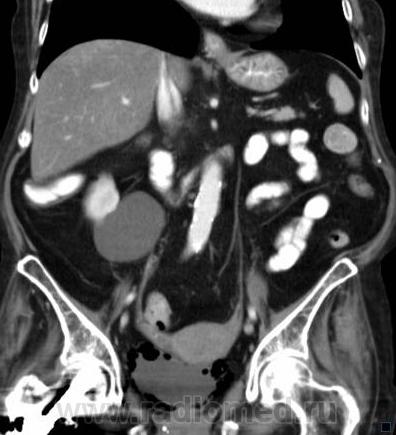

О чём могут говорить такие "газовые структуры" в области мочевого пузыря?

Наличие газа в мочевом пузыре может говорить о многом. Например стоял катетр Фолея, состояние после цистоскопии, эмфизематозный цистит, наличие фистулы.

А, чем именно, будет характеризоваться эмфизематозный цистит? При нем "пузырьки газа" локализуются в слизистой оболочке или где?

В просвете, может быть и в самой стенке. Смотрите здесь:

процесс в стенке в данном случае.

У женщины киста правой почки, подозрение на жировой гепатоз, стержень в головке и шейке правого бедра (остеосинтез). А про воздух возле/в стенке мочевого пузыря... не было ли оперативного вмешательства в малом тазу? И без аксиальных срезов явно я бы не сказала, где конкретно воздухblush...

Фик с ней с кистой... И какая разница аксиалы и короналы... Да, толстоваты срезы, эффект усреднения. Но я бы думал в сторону язвенного/гангренозного цистита (эмфизематозного цистита). Естественно, анамнез и клиника и всё встанет на свои места. На состояние после катерера не очень похоже...